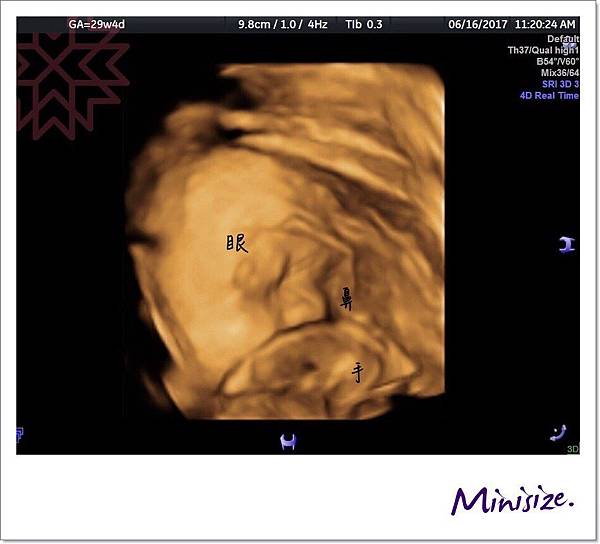

Timo小寶寶不開心

怎麼樣都不願意大方露出小臉蛋

29週的Timo 體重增加到1511克

剛開始直接面向內側睡覺

醫生搖肚皮請寶寶變換姿勢

手手始終在面前不肯放下

原來不只有麻麻不耐飢餓

寶寶餓過頭也是會翻臉的

以後麻麻一定先填飽肚子後再去產檢!!